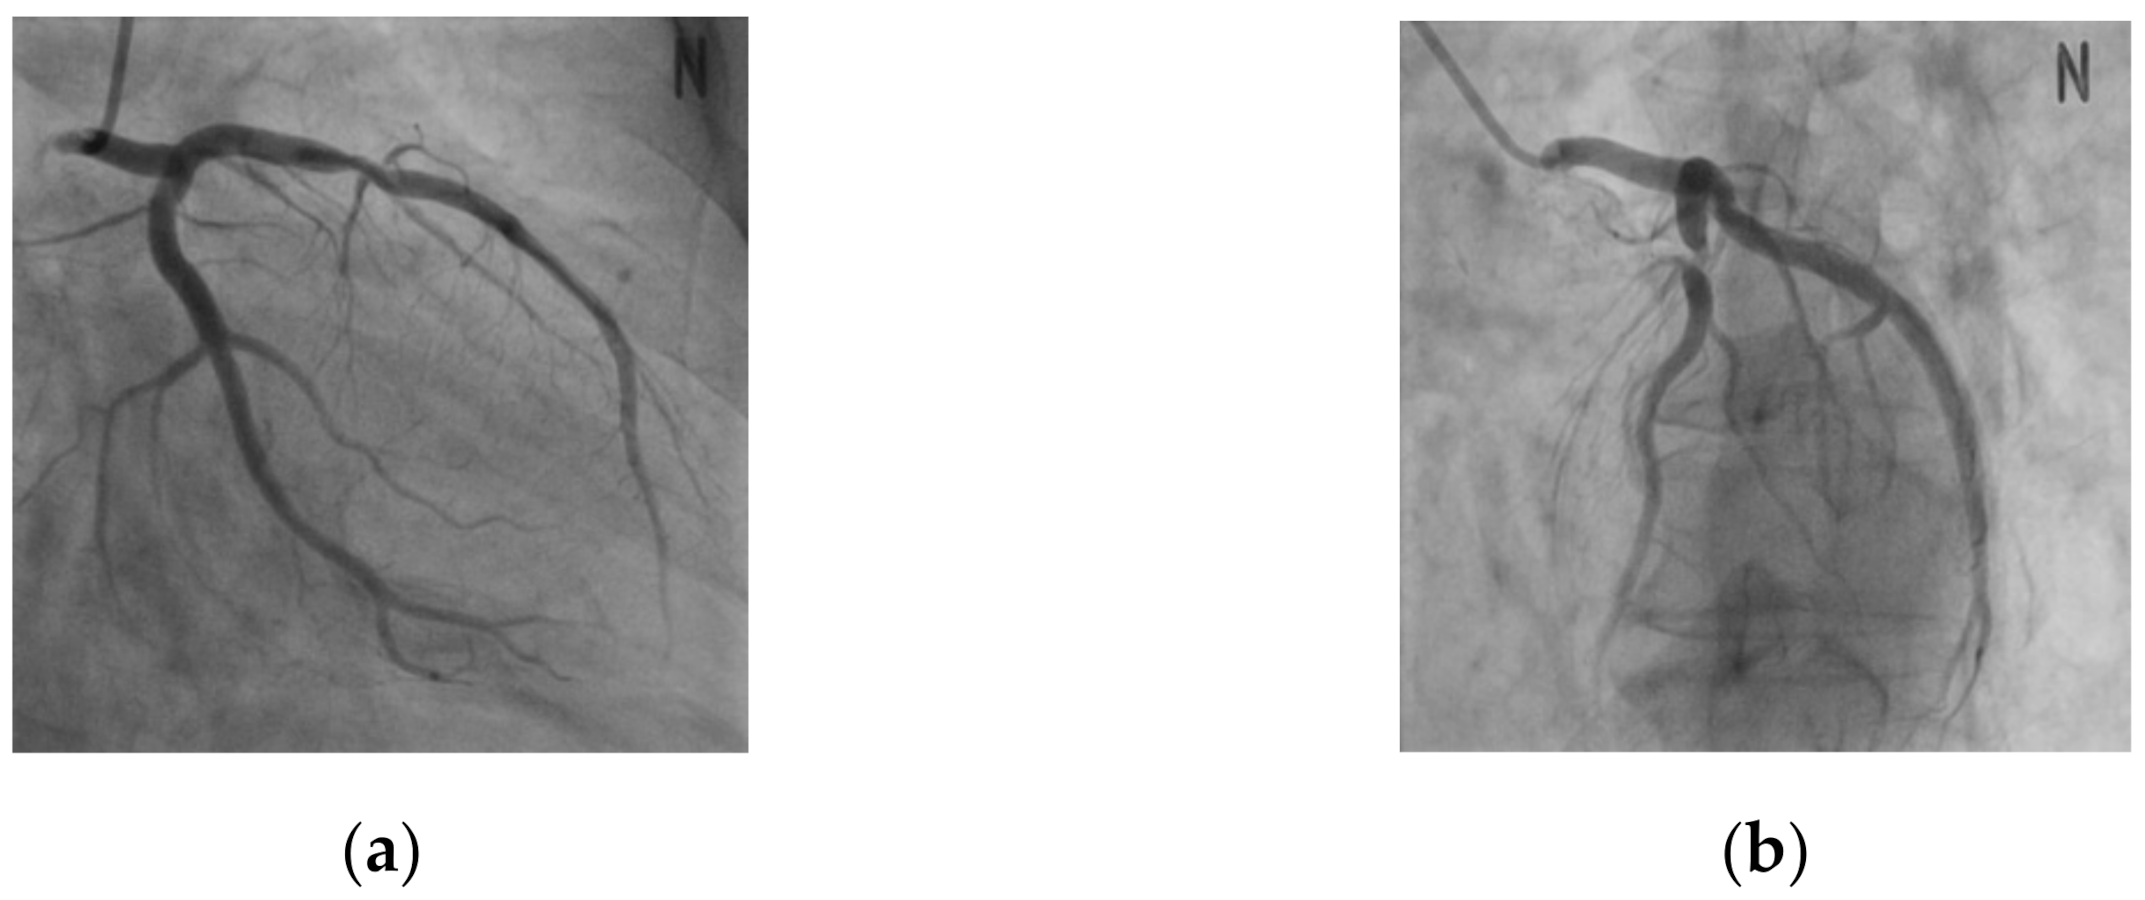

In this study, data from a total of 68 patients were used, and the CTA images of both the left coronary artery (LCA) and right coronary artery (RCA) were used in the case of 27 patients, while the CTA images of either the LCA or RCA were used in the case of 11 patients. For the XA image, 394 series of images at different angles were captured from the 68 patients. Figure 6 shows a series of XA images with different angles for the same patient’s data.

Figure 6. XA Images with different angles for the same patient. (a) Primary angle: −29.3, secondary angle: −18.7. (b) Primary angle: 42.6, secondary angle: 15.8.